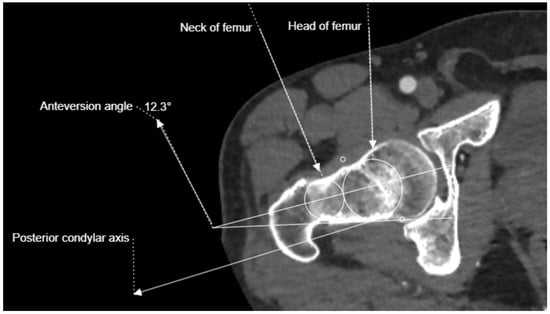

2.3. Imaging and Measurement Methods